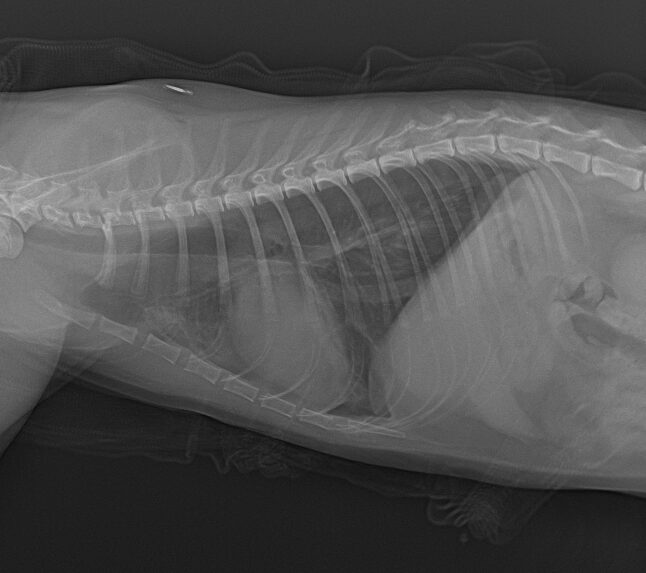

症例は生後約半年の猫で7階から落下したとのことで来院しました。

落下の衝撃で肺に穴が空いているようで気胸になっていました。気胸は程度により、無治療、ドレーン挿入、肺葉切除など様々なレベルの治療を行いますが、今回の症例は数日間ドレーンにより空気と胸水を抜去することで穴を塞ぐことができました。